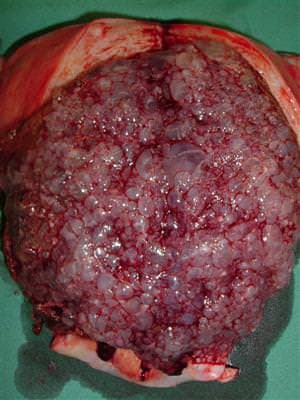

Mol Hidatidiform Hastalığı

Mol Hidatidiform Nedir? Mol gbeliği Nedir? ( Gestasyonel Trofoblastik Hastalık) Trofoblastik hastalık; kadın yumurtasının, bir genetik kromozom...